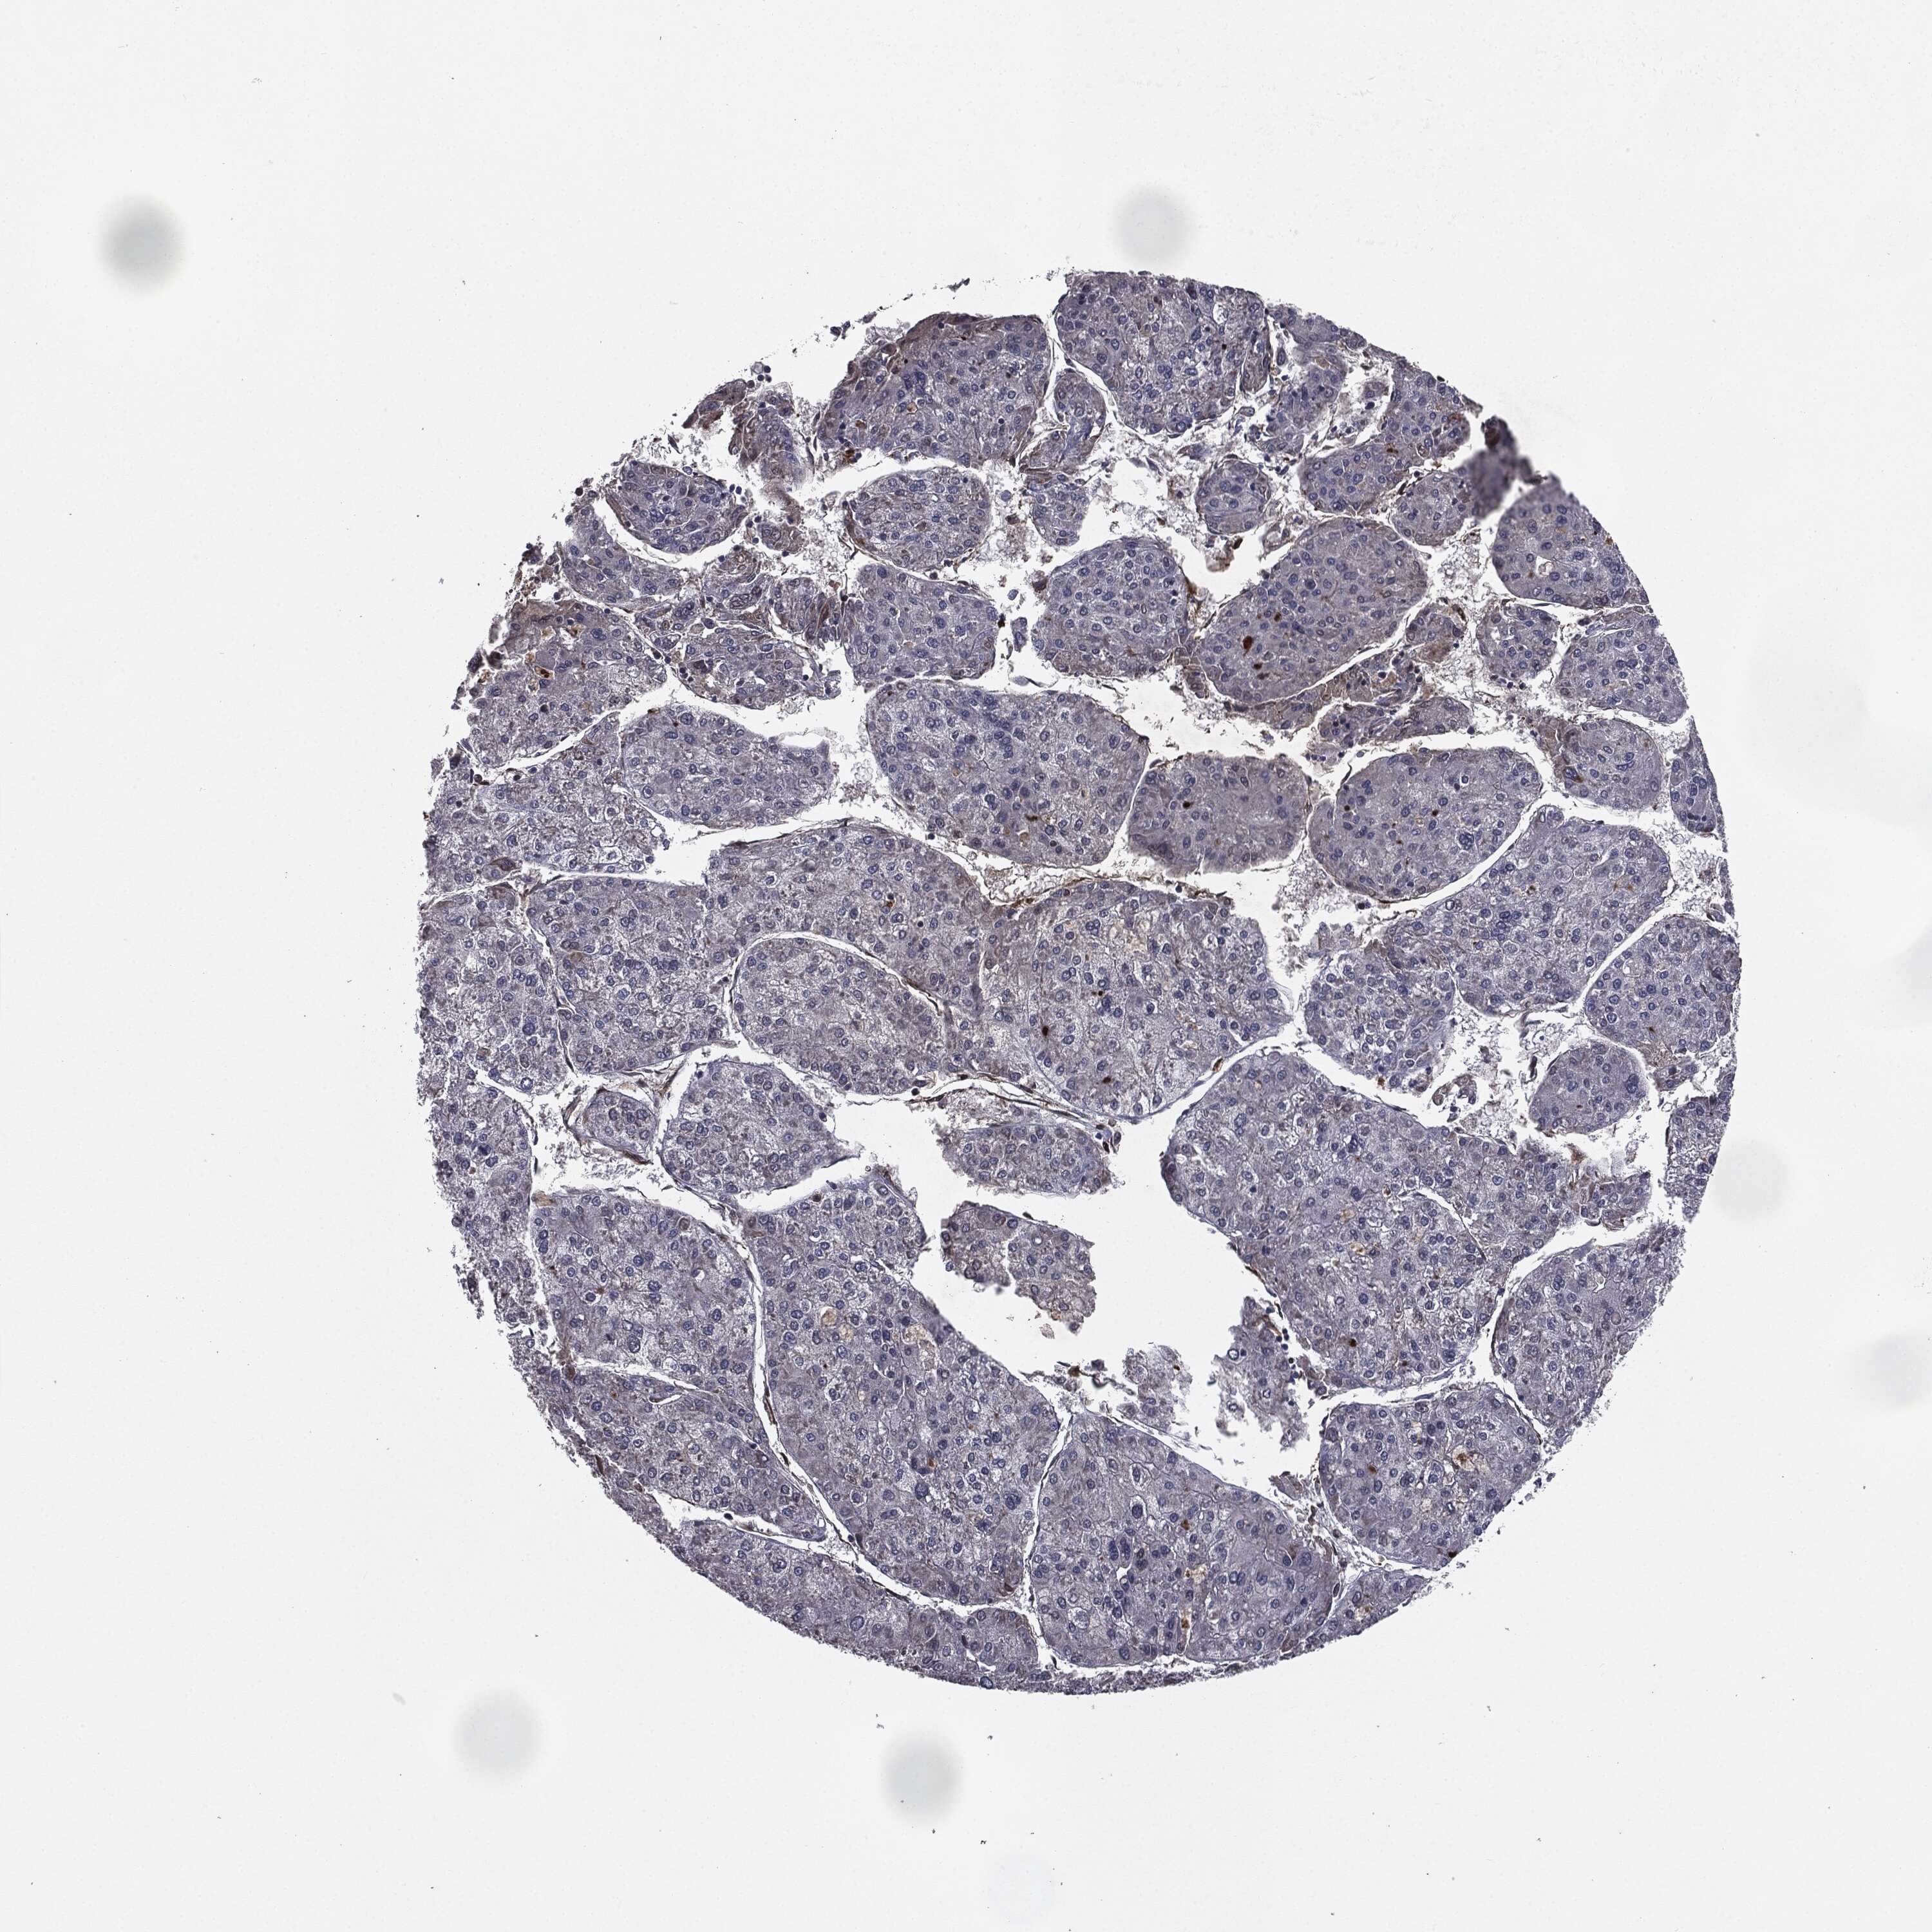

LIVER CANCER - Protein expressioni

A mouse-over function shows sample information and annotation data. Click on an image to view it in a full screen mode. Samples can be filtered based on level of antibody staining by selecting one or several of the following categories: high, medium, low and not detected. The assay and annotation is described here.

Note that samples used for immunohistochemistry by the Human Protein Atlas do not correspond to samples in the TCGA dataset.

Antibody stainingi

Antibody staining in the annotated cell types in the current human tissue is reported as not detected, low, medium, or high, based on conventional immunohistochemistry profiling in selected tissues. This score is based on the combination of the staining intensity and fraction of stained cells.

Each image is clickable and will lead to virtual microscopy that enables deeper exploration of all samples and also displays staining intensity scores, fraction scores and subcellular localization as well as patient and tissue information for each sample.

Antibody HPA052606

Antibody HPA077139

Staining

High

Medium

Low

Not detected

Intensity

Strong

Moderate

Weak

Negative

Quantity

>75%

75%-25%

<25%

None

Location

Nuclear

Cytoplasmic/membranous

Cytoplasmic/membranous,nuclear

Carcinoma, Hepatocellular, NOS

Cholangiocarcinoma